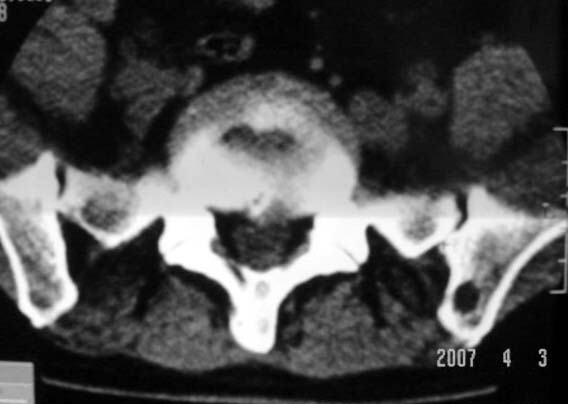

行腰椎间盘检查时,发现左侧髂骨后缘一类圆形低密度影,ct值约负43hu。

左髂骨后缘髓内囊性低密度影ct值-43,考虑髂骨髓内脂肪瘤。应该是少见病变,但跟骨脂肪瘤有过报道。

既然是负值,那么考虑骨纤维结构不良、骨囊肿就不太合适了。由战友考虑骨髓窦,个人认为觉得也不妥。理由很简单,骨髓窦是一种骨骨松质内小梁发育稀少或缺失形成的空腔,因而张力较小,形态可以不规则。而本例病变形态规则呈圆形,且边缘轻度硬化,这些度不符合骨髓窦的特征。所以本例应该考虑骨内脂肪瘤